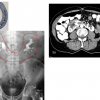

– Hai thận xoay trục, cực dưới hướng vào trong phía cột sống.

– Đài bể thận bình thường hướng lên trên ra ngoài => hướng xuống dưới.

– Phần nối hai cực dưới là nhu mô hoặc dải xơ vắt ngang phía trước cột sống.

=> Case lâm sàng 1:

=> Case lâm sàng 2: